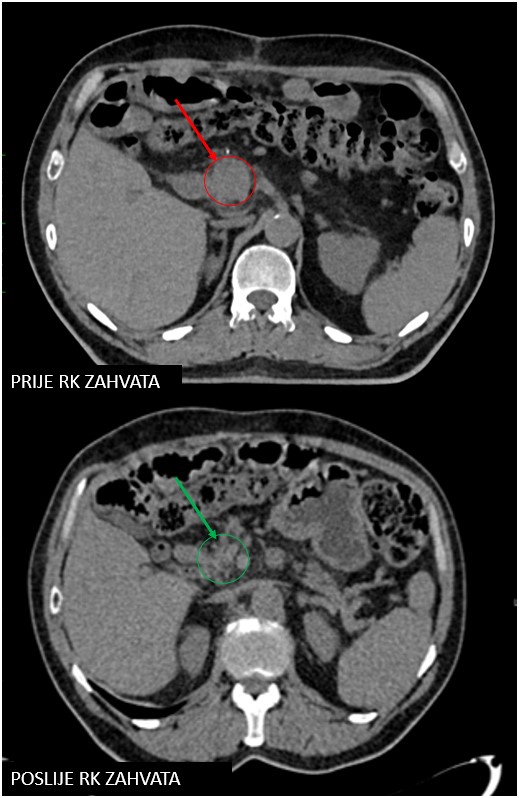

gušterača 59 3agušterača 59 3b

Rezultat – 45 mjeseci nakon RK

Potpuni nestanak tretirane lezije